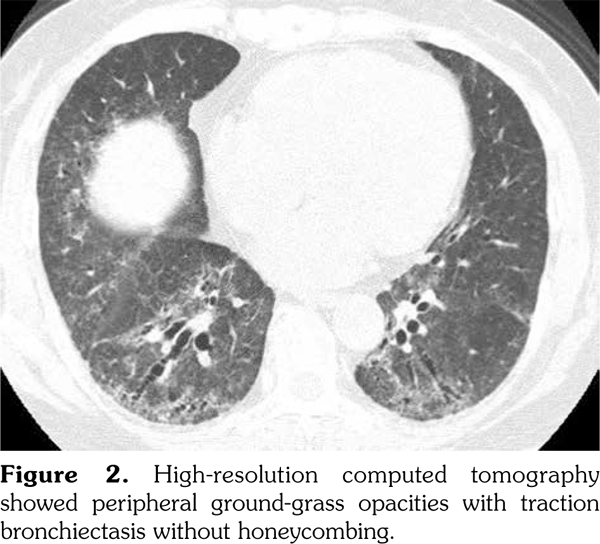

A 72-year-old female patient was admitted for rapidly progressive glomerulonephritis. Three years previously, she was first suggested to have interstitial pneumonia on health checkup. However, she did not visit the office because she was asymptomatic. One year later, the patient visited the hospital for exertional dyspnea. She also had noticed Raynaud’s phenomenon and sicca syndrome for several years. Chest X-ray showed permeability loss of the lower lung fields (Figure 1). High-resolution computed tomography of the lung showed ground-glass opacities with traction bronchiectasis in the peripheral lungs, without honeycombing, which was compatible with nonspecific interstitial pneumonia (Figure 2); at that time, laboratory test showed negative result of MPO-ANCA (<1.0 U/mL; normal <3.5 U/mL) (Figure 1). The test for anti-nuclear antibody was positive at 80 folds for homogeneous and speckled pattern (normal range <40 folds); however, the results for anti-topoisomerase, anti-centromere, anti-ribonucleoprotein, anti-ribonucleic acid polymerase III, and anti-Sjögren syndrome antigen A/Ro and anti-Sjögren syndrome antigen B/La antibodies were all negative. Accordingly, the diagnosis of interstitial pneumonia associated with rheumatic disorders was not considered likely. The results of bronchoalveolar fluid analysis, including cellular profiles, cytology, and culture for bacteria and mycobacterium, were not remarkable. Transbronchial biopsy showed no pathogenic findings. Therefore, patient was considered to have IIP. She was followed-up without therapy. Ten months before admission, she developed polyarthralgia and was suspected to have rheumatoid arthritis following a positive result for rheumatoid factor; at that time, testing for MPO-ANCA showed positive conversion, at 9.0 U/mL. The dipstick test, however, showed negative result for uric blood and protein. Therapy with tacrolimus and celecoxib alleviated her symptoms. Her medical history included cholecystectomy and lumbar compression fracture, and her medication regime comprised tacrolimus, celecoxib, famotidine, and sulfamethoxazole/trimethoprim. She denied a history of fever, sensory disturbance, or rash. On physical examination, body temperature was 36.3°C, blood pressure was 154/94 mmHg, and pulse rate was 95/minute. Respiration rate was 12/minute on room air. There were fine crackles on the lung bases and edema of the legs. No abnormal findings were observed on the heart, the abdomen, the skin or the neuromuscular system. Laboratory test results were as follows: white blood cell, 11130/μL (neutrophils 75.5%); C-reactive protein, 6.13 mg/dL; urea nitrogen, 42.2 mg/dL; creatinine, 4.23 mg/dL; urine protein, (2+); spot urine protein/creatinine ratio, 2.7; and 24-hour urinary protein excretion, 2.0 urine sediment showed urinary erythrocytes of >300/high-power field, red blood cell cast of 5-9/high-power field, and granular cast of 1-4/high-power field. The level of MPO-ANCA was highly elevated at 71.2 U/mL. X-ray of the hands did not show significant findings of erosion or joint space narrowing. A retrospective review of chest radiographs revealed slow progression of the pulmonary fibrosis (Figure 1). Computed tomography of the lung also revealed progression of pulmonary fibrosis. Renal biopsy showed necrotizing crescentic glomerulonephritis, leading to the diagnosis of microscopic polyangiitis (MPA). Methylprednisolone pulse therapy, followed by high-dose prednisolone, and intravenous cyclophosphamide improved renal function. Four months after therapy, the levels of urea nitrogen and creatinine were 29.8 mg/dL and 1.55 mg/dL, respectively. A spot urine protein/creatinine ratio was 2.4, while urinary sediment was inactive.